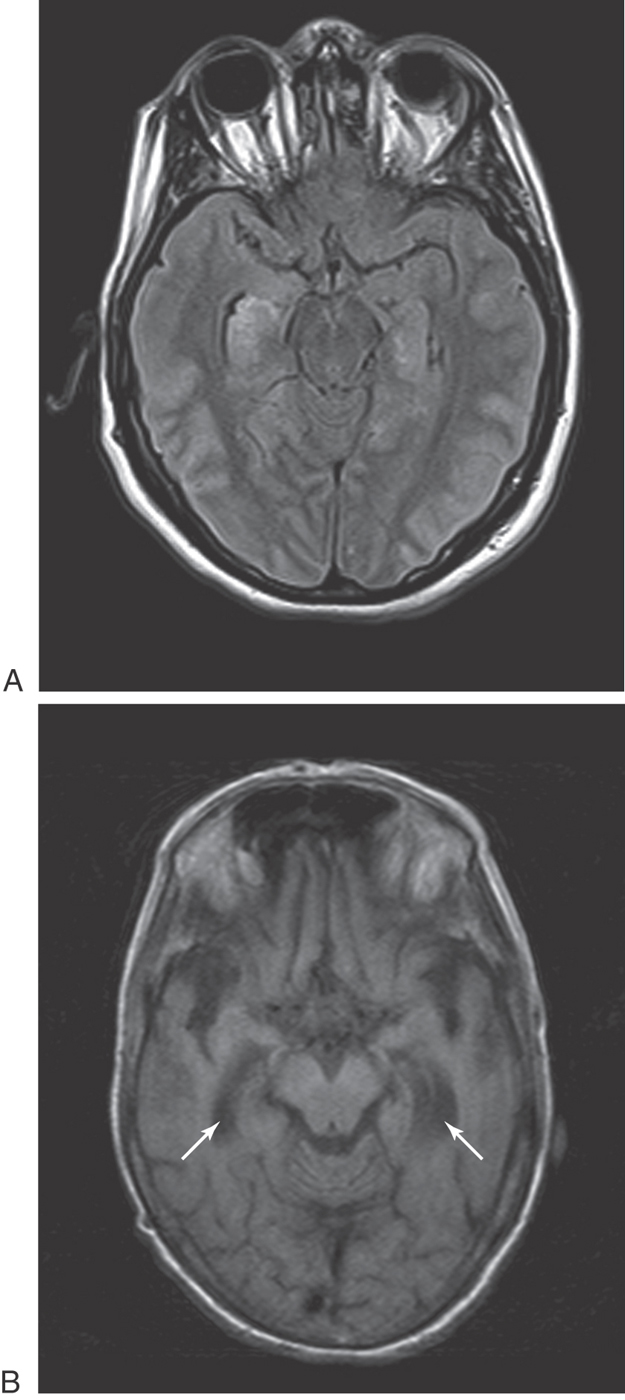

Bilateral damage to the hippocampal formation sometimes occurs in victims of heart attack, near-drowning, or severe hypoglycemia as a result of cerebral ischemia (Fig. 31-6A). The part of the hippocampal formation most vulnerable to anoxia during an ischemic episode is the CA1 area. The CA1-subiculum interface region is referred to as the Sommer sector in pathologic conditions. Affected patients retain memories for events occurring after the ischemic episode. Consequently, they also have difficulty learning new concepts because the new information is not retained (remembered) long enough to become a long-term memory.

Figure 31-6. Axial magnetic resonance image showing hyperintensities in both hippocampi, slightly brighter on the right than on the left, due to severe hypoglycemia (A). In B, a T1-weighted axial magnetic resonance image, note the atrophy of both hippocampi with enlarged temporal horns (arrows) and atrophy of the orbitofrontal cortex in a patient with Alzheimer dementia.

Another condition in which loss of memory and cognitive function is particularly obvious is Alzheimer disease (AD). This disease is characterized, in part, by the presence of neurofibrillary tangles, neuritic plaques, and neuronal loss in specific brain regions (Fig. 31-6B). The subiculum and entorhinal cortices are among the first sites in which these abnormalities appear. As a result, the relay of information through the hippocampal formation is impeded. It is believed that this damage is at least partially responsible for the difficulties with declarative memory characteristic of AD. Poor recall of recent events or incorporation of new facts occurs early in AD. Long-term memory impairment and behavioral changes occur in later phases. Procedural or implicit memory, the motor skills for performing tasks, is relatively spared because this type of memory is encoded by the basal ganglia and cerebellum.

Defects in memory can also result from prolonged thiamine deficiency. This B vitamin deficiency typically seen in the context of chronic alcoholism, cancer cachexia, or any prolonged state of malnutrition causes a characteristic pattern of degeneration in the brain (Fig. 31-7). Typically, the mammillary bodies are involved, with some incursion into the dorsomedial nucleus of the thalamus and the columns of the fornix. There is also a loss of neurons in the hippocampal formation (Fig. 31-7). These patients with Korsakoff psychosis (alcoholic dementia) show a defect in short-term memory and consequently also in long-term memory for events occurring since the onset of the disease. They may appear demented, and they are prone to confabulation; that is, they tend to string together fragments of memory from several different events to form a synthetic “memory” of an event that never occurred (Table 31-2). Korsakoff psychosis is irreversible. Thiamine deficiency may also be manifested more acutely as a triad of eye movement abnormalities, ataxia, and confusion known as Wernicke encephalopathy, which is reversible with thiamine replacement. Table 31-2 contrasts the acute and chronic neurologic consequences of thiamine deficiency. In severe cases, patients may present with the Wernicke triad accompanied by profound memory loss; this condition is called Wernicke-Korsakoff syndrome.

Figure 31-7. Axial computed tomography scan showing severe atrophy of temporal and frontal lobes as well as prominent cerebellar folia (also a sign of atrophy) in a patient with alcohol dementia. Also note the enlarged temporal horns of the lateral ventricles (arrows).